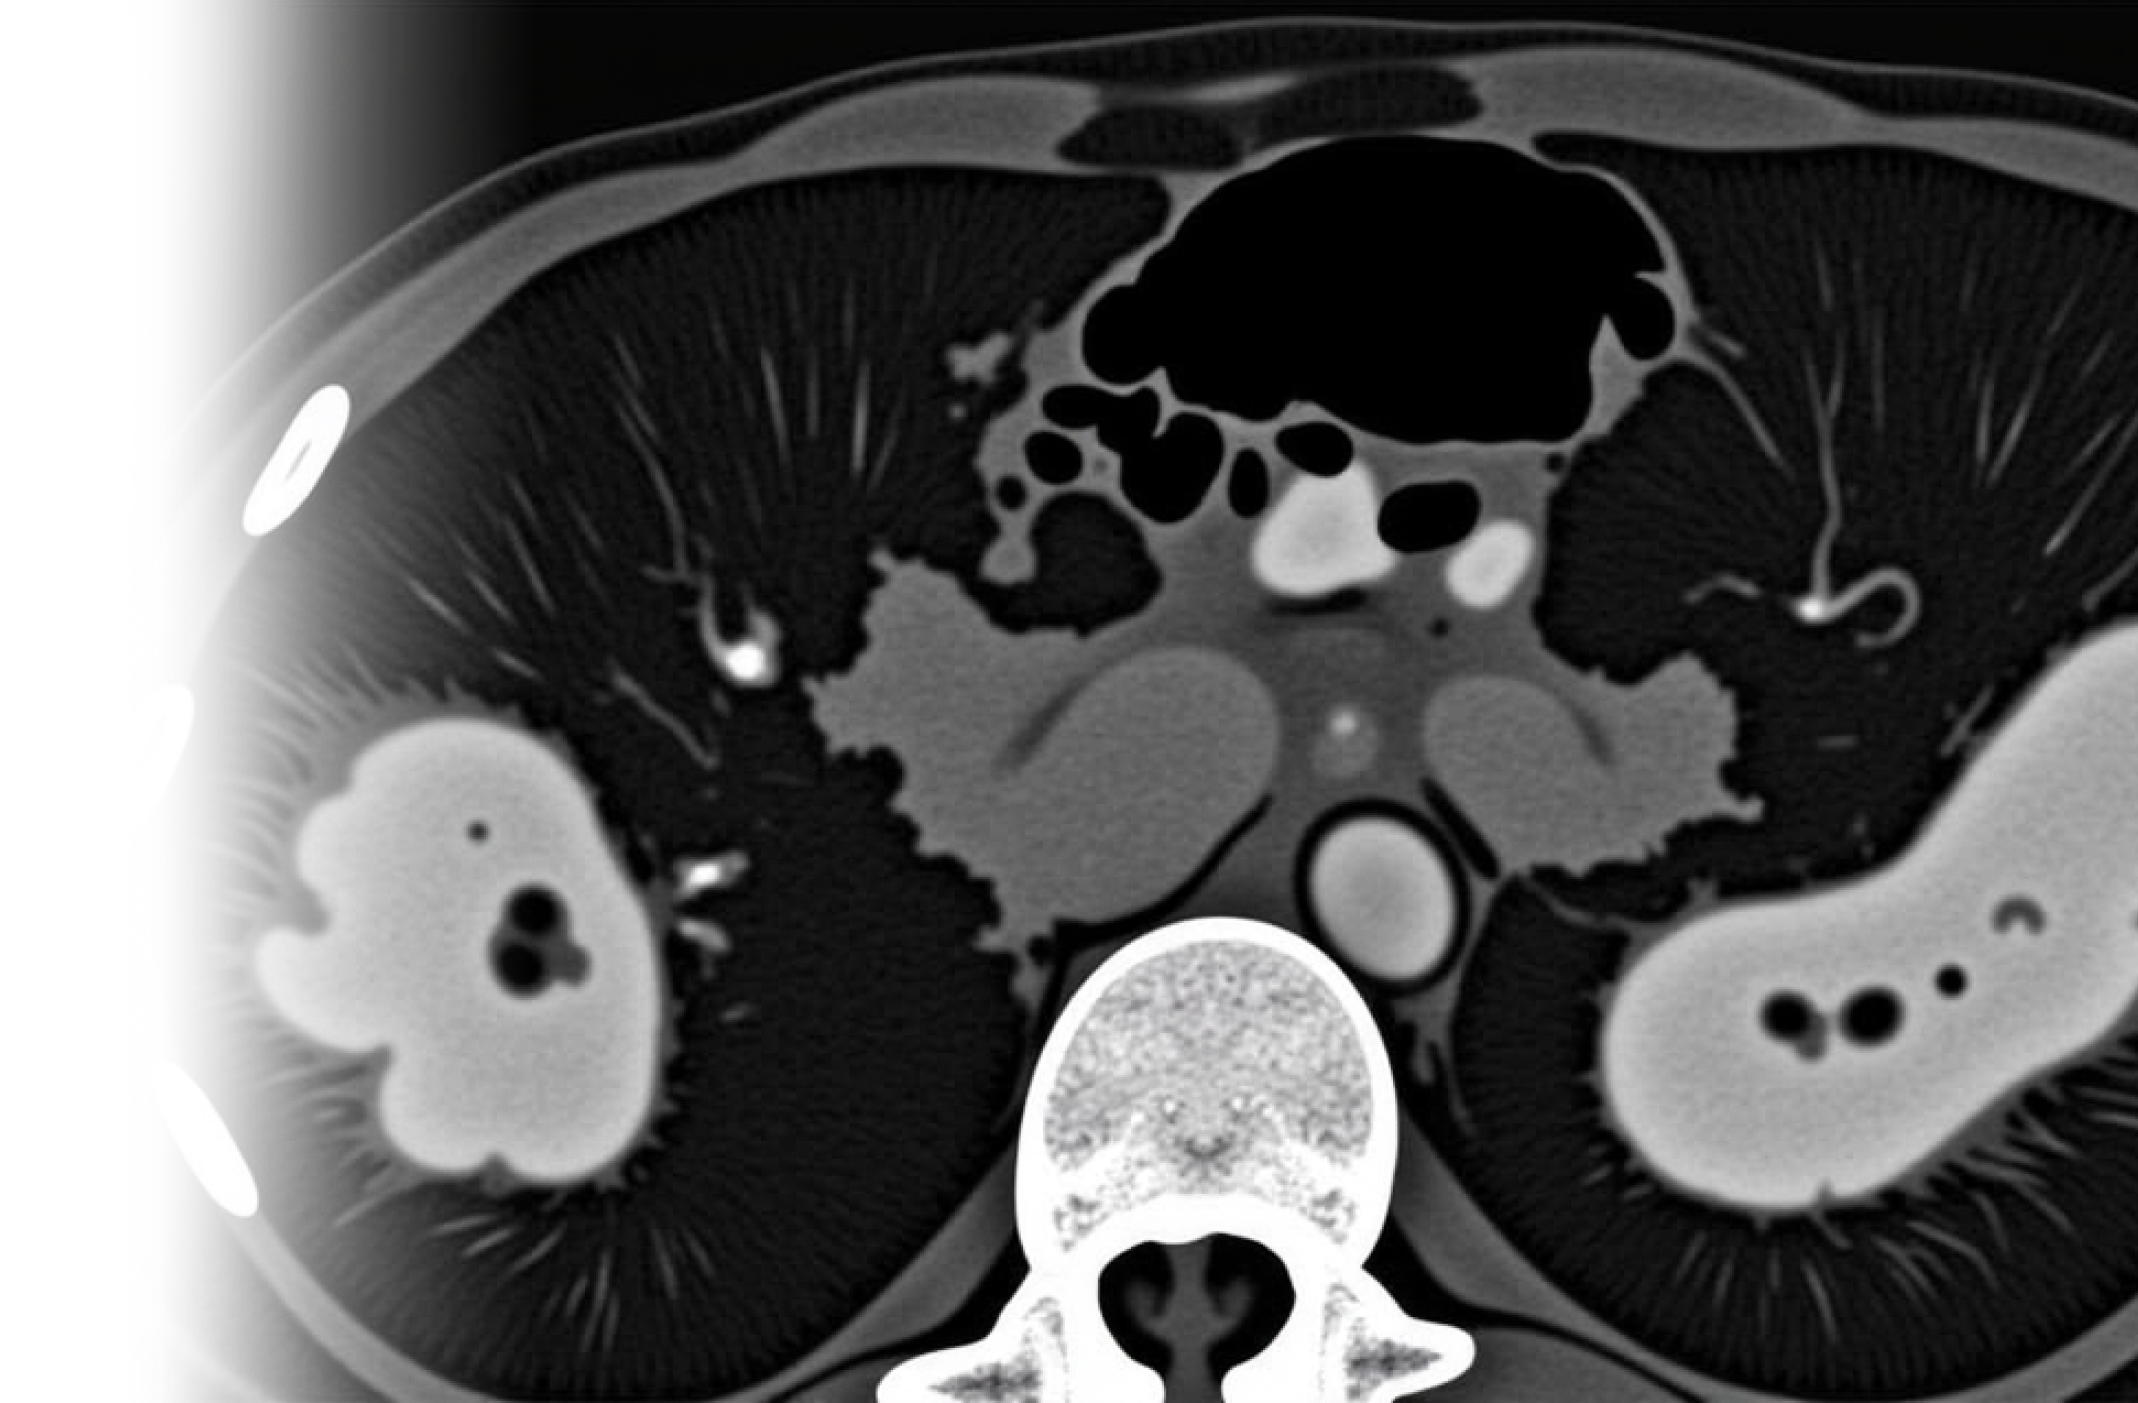

Компьютерная томография органов грудной клетки, брюшной полости и забрюшинного пространства с контрастированием – важный метод исследования органов грудной клетки, брюшной полости с внутривенным введением йодного контрастного препарата с помощью автоматического инжектора и с последующим пофазным сканированием.

• оценка патологий паренхимы легких, органов средостения, органов брюшной полости, забрюшинного пространства;

• оценка распространенности онкологического процесса.

Пациенту внутривенно вводится контрастное вещество, которое обеспечивает более качественную видимость органов на получаемых снимках, что позволяет выявить даже самые незначительные изменения в исследуемой области.

После этого пациент ложится на стол сканера, который постепенно перемещается в аппарат. Во время сканирования следует лежать неподвижно, чтобы получаемые трехмерные изображения были четкими и неискаженными.